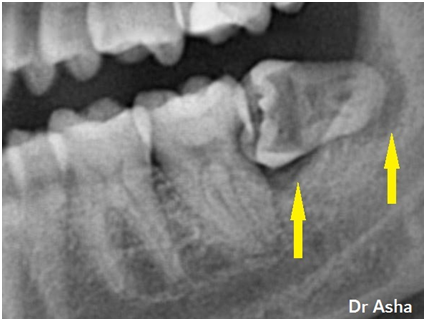

This is the X-ray of the same case.

Decay had begun in between the teeth and hollowed out the horizontally impacted wisdom tooth and caused decay on the back surface of the 2nd molar. The extensive decay has caused infection that has destroyed bone around the roots and in-between the teeth. This is indicated by the yellow arrows.

c) This close-up X-ray shows how food debris & bacteria stuck between the teeth have caused extensive decay of both the wisdom tooth and the tooth in front of it.

In this case, both teeth had to be removed.